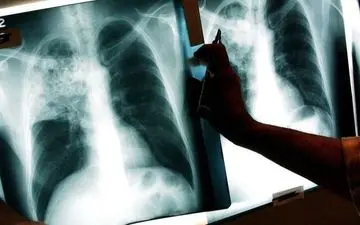

سرپرست مرکز بهداشت شهرستان کاشان گفت: بر اساس آمار موجود، در ششماهه نخست سال جاری، ۱۷ بیمار جدید مبتلا به بیماری سل…

معاون بهداشت دانشگاه علوم پزشکی زاهدان گفت: بیماری سل خوشبختانه قابل درمان و تشخیص و درمان آن در مراکز خدمات جامع…

میزان بروز سل در ایران ۱۰ برابر کمتر از آمار جهانی است و از هر ۱۰۰ هزار نفر، ۱۴ مورد در معرض ابتلا به این بیماری قرار…